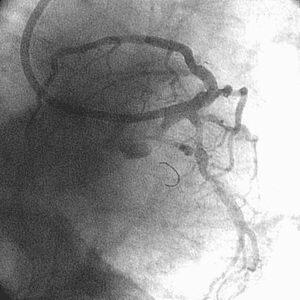

高度石灰化#1~#2と同#6/#9に対するRotablator依頼で他院から紹介され、PCIを

施行した86歳の男性です。3日前にRCAへRota-SESして、今回#6/#9へのPCIでした。

Baselineが『ChoicePT2BsLn』の3枚です。

7F lTFA(Arrow金属シース55cm)で7F Mach1 CLS4.0を使用、#9→#6の順に1.5mm burr

でRotablatorを行ない、2.0mmへサイズアップしました。2.5mmバルーンで#9→#6と拡

張し、#6に3.5mm×23mmのCypherを留置しました。3.5mmバルーンで#6を高圧(最

大22ATM)後拡張し、#9の2.5mmバルーンとともにSimultaneous kissing inflationを

施行、#6、#9ともに良好な開大を得ました。

しかし、KBT直前の像(『ChoicePT2.GW.Prolapse』)では屈曲していただけの#9に挿

入したChoice PT2 LSが、KBT時像からは屈曲とともに先端1cm程度が断裂し

(『ChoicePT2.GW.Fracture』)、#9の末梢枝に遺残してしまいました

(『ChoicePT2.Fnl』2枚)。幸い虚血所見がまったくありませんでしたので手技は終

了とし、術後のCK逸脱もなし、翌日お元気に退院されました。